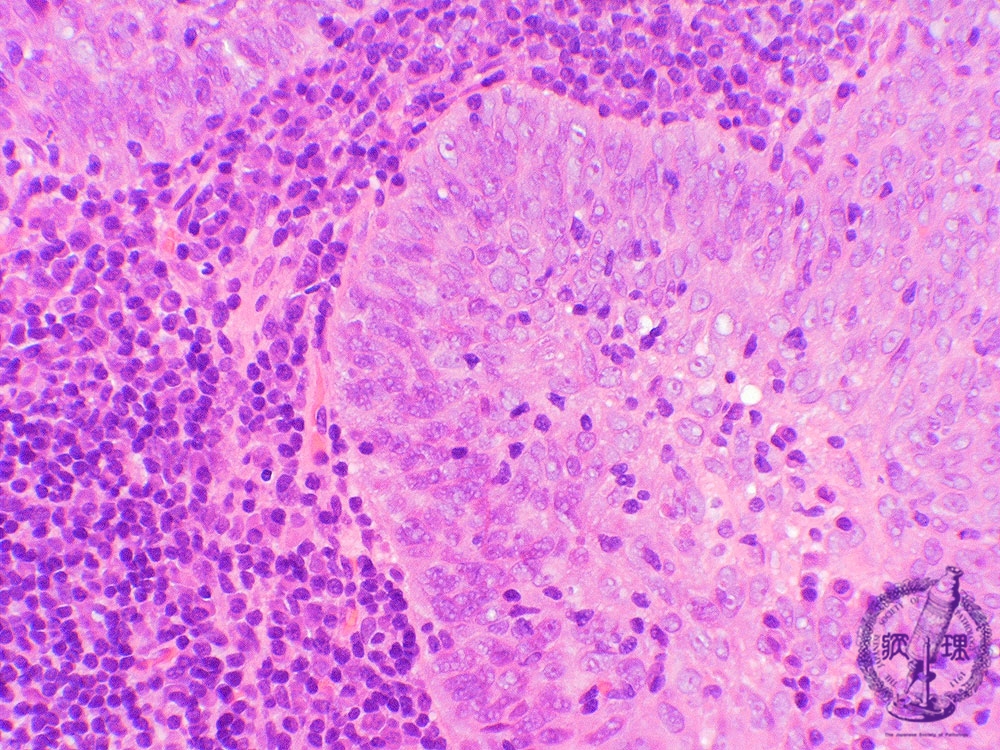

- ★(4)Nasopharyngeal carcinoma (lymphoepithelioma)

e tumor cells in this example show better differentiation as compared to the tumor cells in undifferentiated carcinoma. The tumor cells are invasive, show sheet-like proliferation and form large alveolar lesions (asterisk). Central nucleoli are not prominent and show similar features of squamous cell carcinoma.